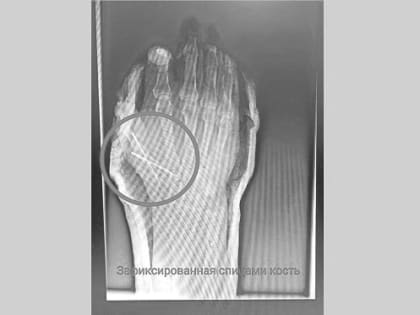

В Татарстане врачи спасли от ампутации палец 54-летнего мужчины, отрезанный болгаркой

Врачи Нижнекамской центральной районной многопрофильной больницы рассказали о спасении 54-летнего пациента, который работая на даче случайно травмировался болгаркой.